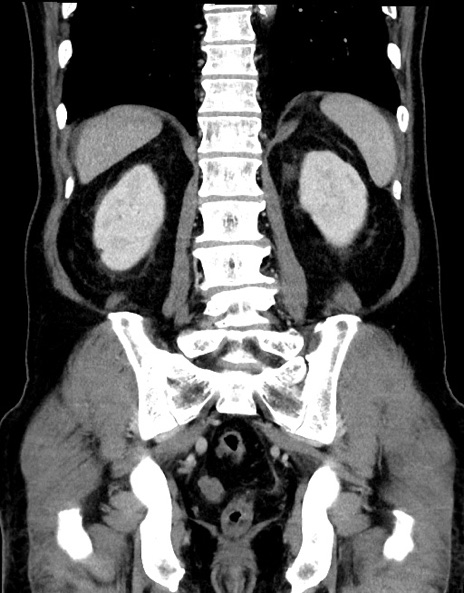

症例15(冠状断像)

【症例】70歳代男性

【主訴】腹痛

【現病歴】今朝から腹痛あり。全体的に痛い。特に左上の方。排ガスが今日はない。冷や汗が出る。

【既往歴】直腸癌術後

【身体所見】左側腹部〜上腹部に圧痛あり。腹膜刺激症状明らかなではない。軽度反跳痛。左下腹部に術後瘢痕あり。

【データ】WBC 7700、CRP 0.02